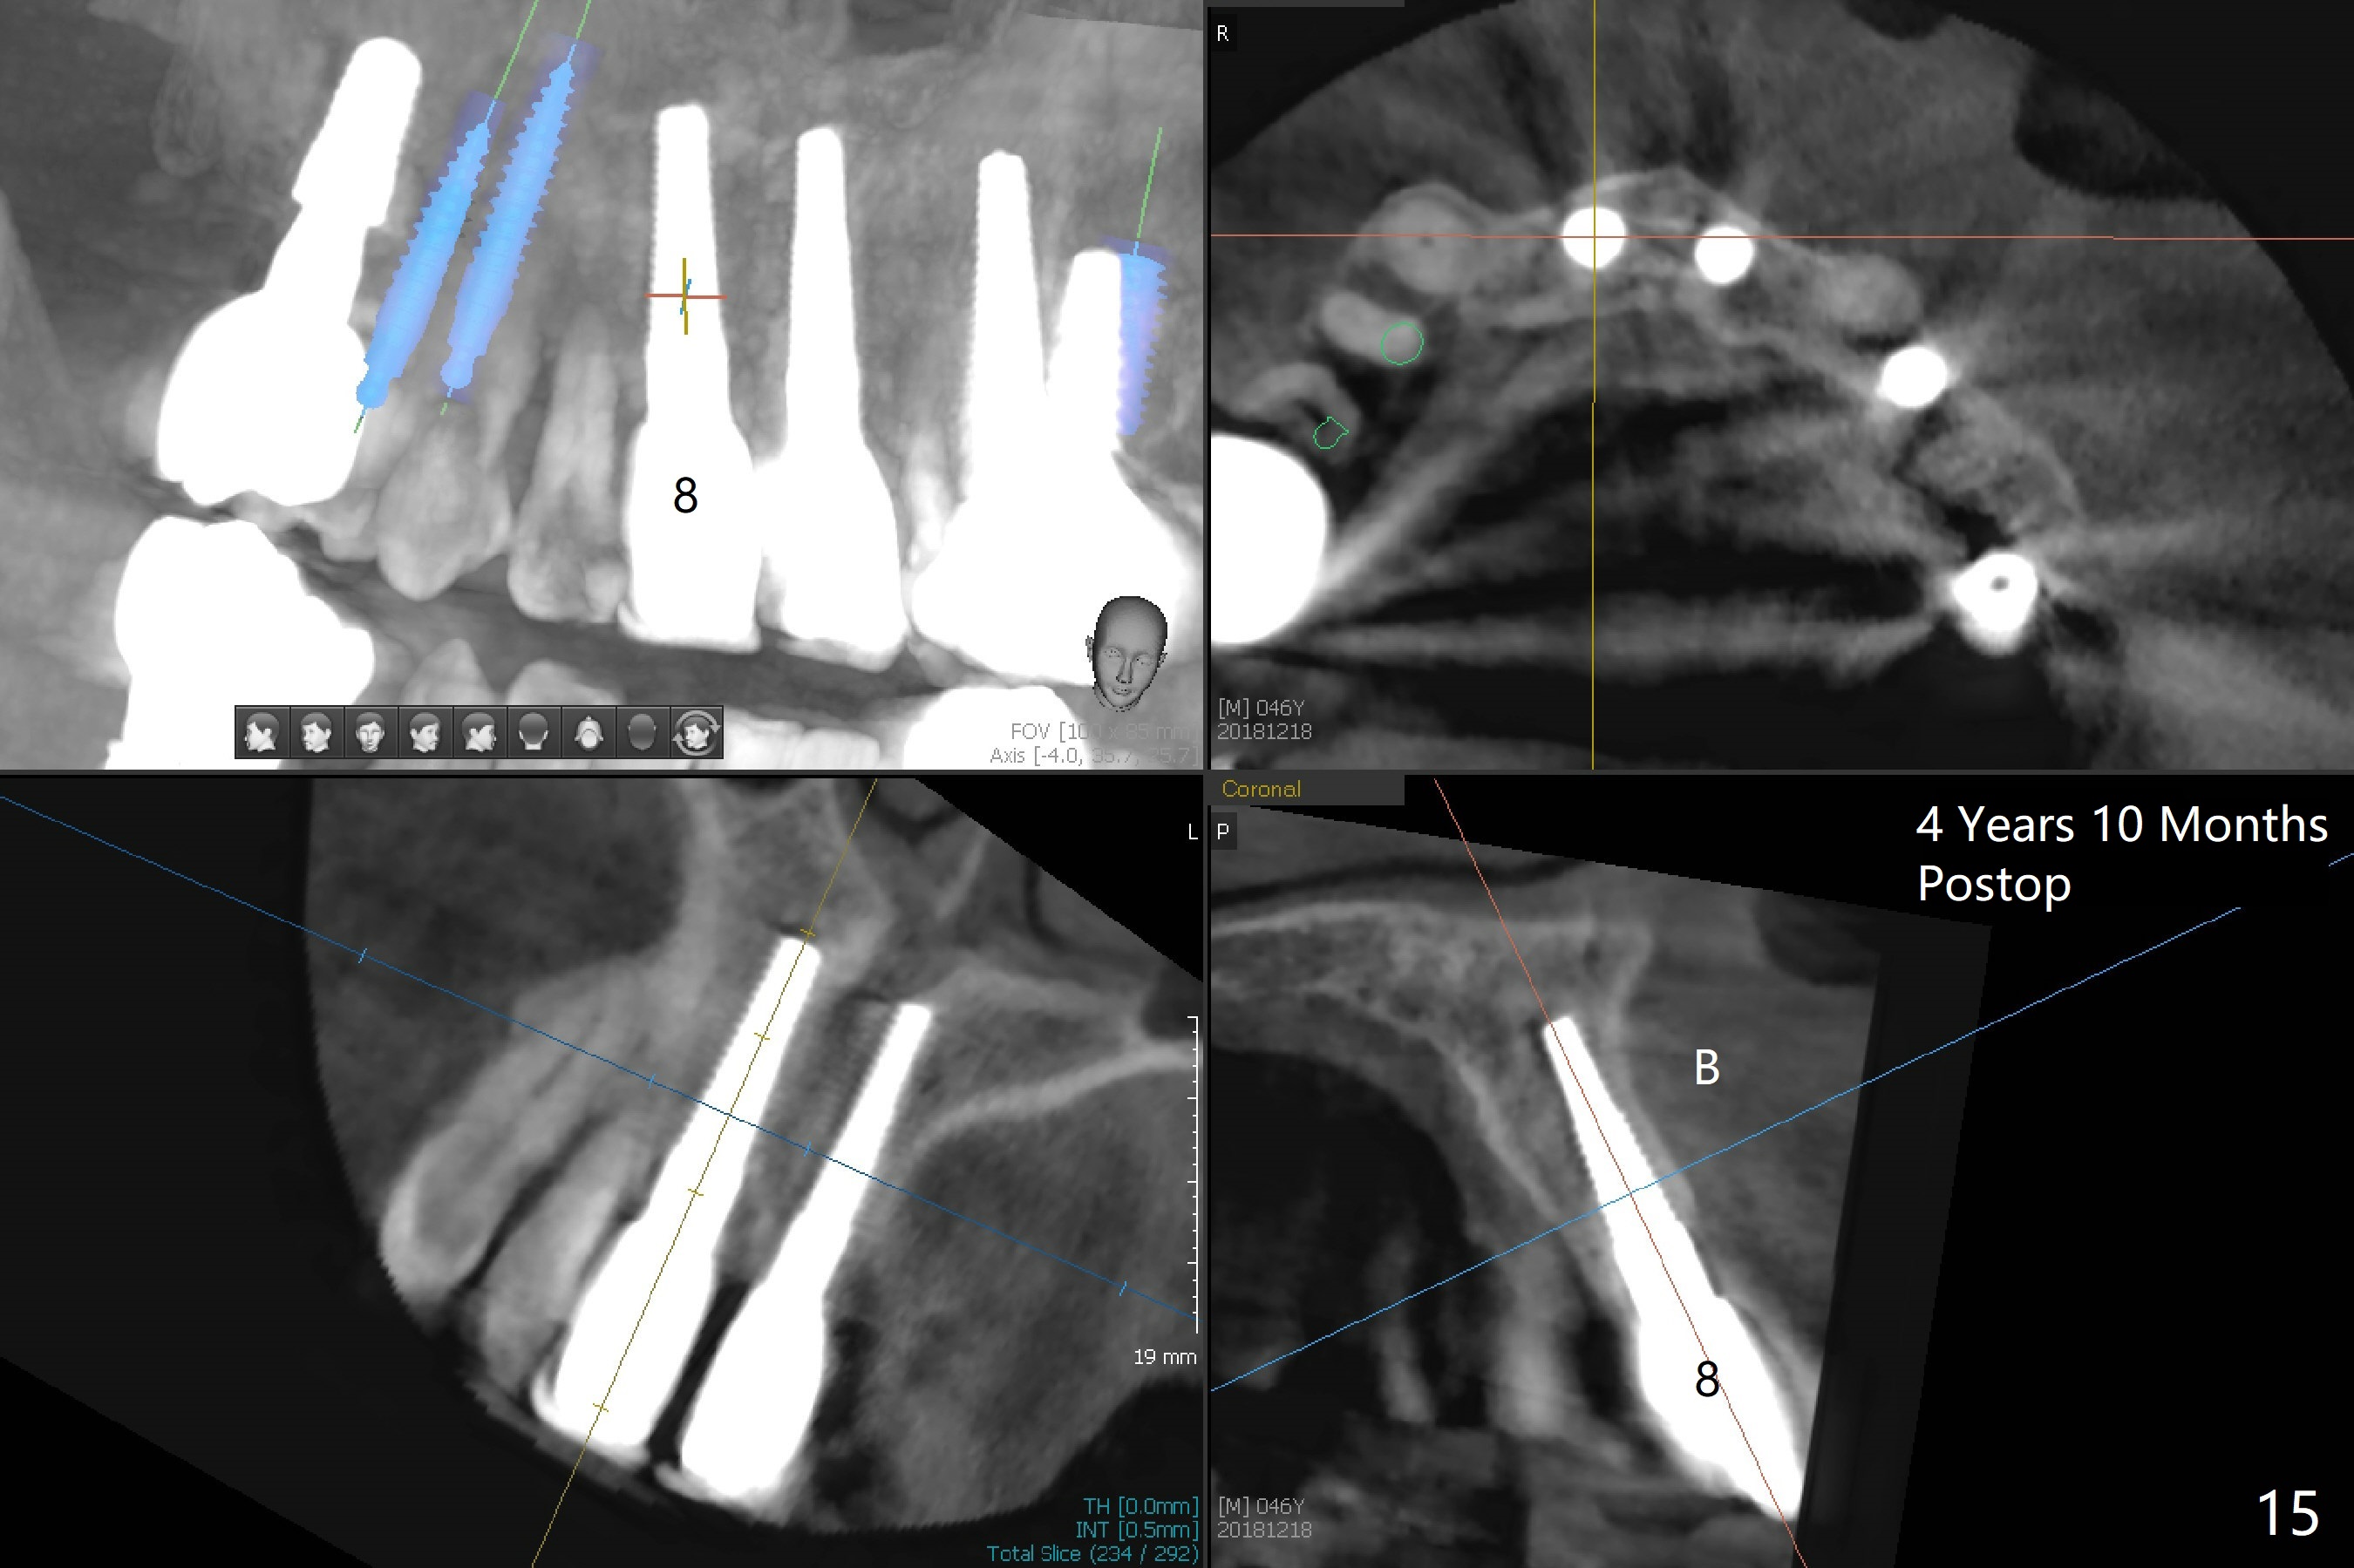

These two anterior implants remain stable 2 months 20 days postop, since one of the immediate provisionals has incisal chip (Fig.11 *) while both of them are splinted (<) to increase retention. There is no complain about paresthesia around the incisal papilla due to separation of the nasopalatine nerve. Mesiodens sockets disappear 7 months postop (Fig.13). There is no bone loss 2 years 9 months postop (Fig.14 panoramus) or 4 years 10 months postop (Fig.15,16 CT). The buccal gingiva is reddish and swollen with bleed on probing and history of pain 7 years post cementation (Fig.17). There is no bone loss in PA (Fig.18). The buccal plate at #9 is thinner than that at #8 4 years 10 months post cementation (Fig.19,20).